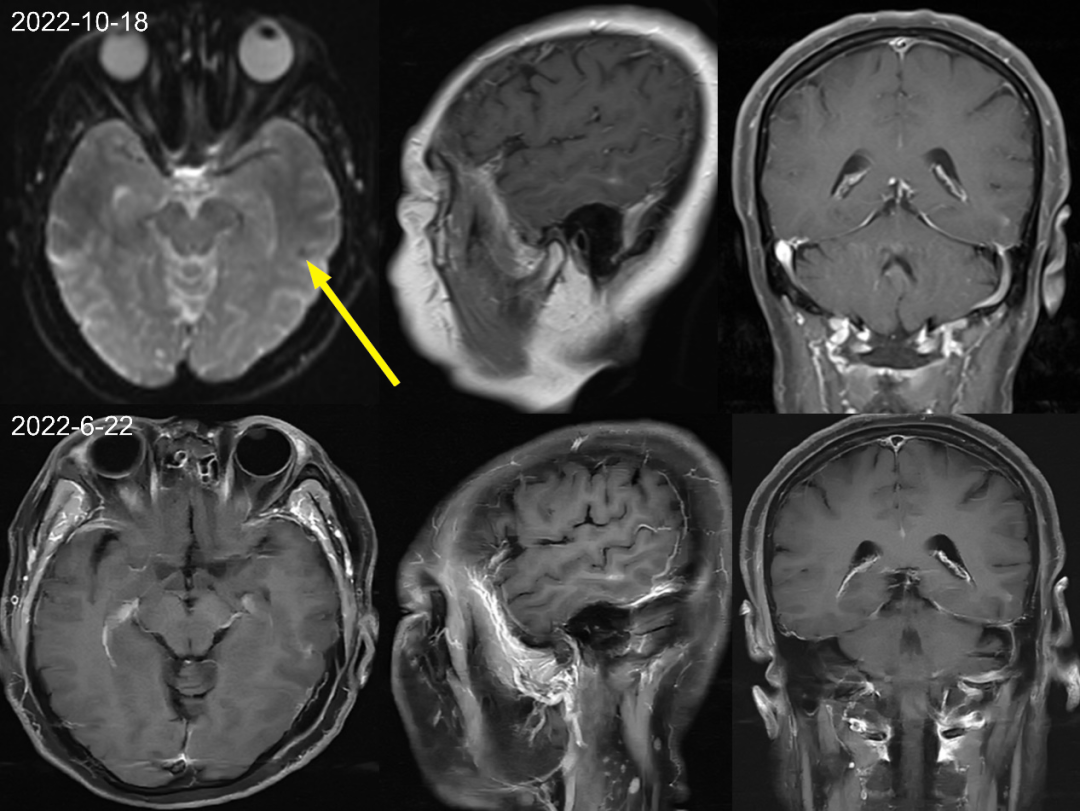

首次检查 2021-1-5 日发现左侧颞叶强化结节,轴矢冠状位都能看到,但是平扫看不到,周围亦未见水肿信号,此时没经验的诊断医生估计会考虑为转移瘤,一直困扰着患者和临床医生。但是在其余 7 次检查中 2021-3-2 至 2022-6-22 一年半多的时间,左侧颞叶强化结节仍然存在,并且基本没啥变化,如果是转移瘤会这么长时间无任何干预都处于一个静止状态吗?,此时是不是需要考虑其他的诊断?,究竟是什么呢,有经验的医生肯定会想到:是毛细血管扩张症。

③常规 MRI 也难以发现病变,约 50% 病例在 SWI 为局部轻微低信号,增强扫描呈轻微刷状或绒毛状、点状及线状强化。

仔细观察本例左侧颞叶强化结节,中心为明显强化,周围为稍淡淡样的强化,此为毛细血管扩张症的特点。